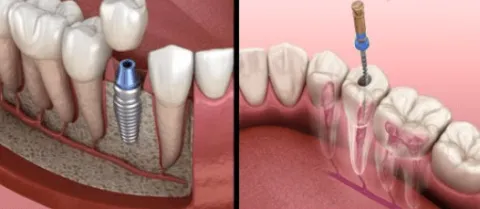

Rotfyllning eller tandimplantat – vad är bäst för dig? När en tand är skadad eller saknas helt uppstår ofta frågan: ska man välja rotfyllning eller tandimplantat? Det är ett beslut som påverkar både funktion, ekonomi och långsiktig munhälsa. På Käkkirurgiskt Centrum Skåne i Malmö möter vi ofta patienter som vill förstå skillnaden mellan dessa två […]

Direktimplantat – när tandimplantat placeras direkt efter tandutdragning

Direktimplantat – när tandimplantat placeras direkt efter tandutdragning Att förlora en tand påverkar inte bara funktionen när man tuggar eller talar, utan också utseendet och ofta självkänslan. Lyckligtvis finns det idag moderna behandlingsmetoder som gör det möjligt att ersätta förlorade tänder snabbt och effektivt. En av de mest avancerade metoderna inom implantatkirurgi är det som […]